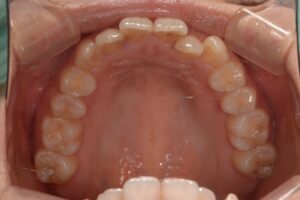

治療前の口腔内写真です。

左上の前歯が上下で噛み合わせが逆転しているのと、下の前歯のがたつきが気になるとのことでした。